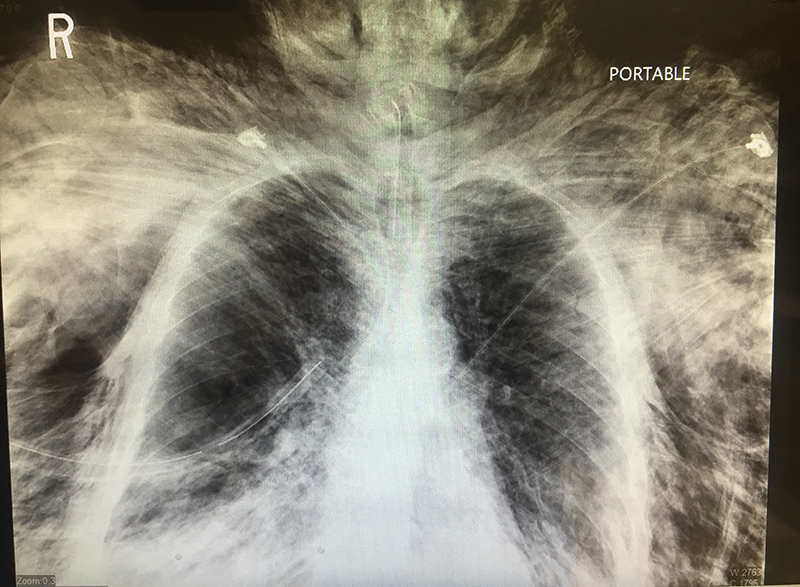

An elderly vent-dependent patient presented to the emergency department with dyspnea, and was found to have a R sided pneumothorax on initial chest x-ray. A chest tube was placed with the following complication.